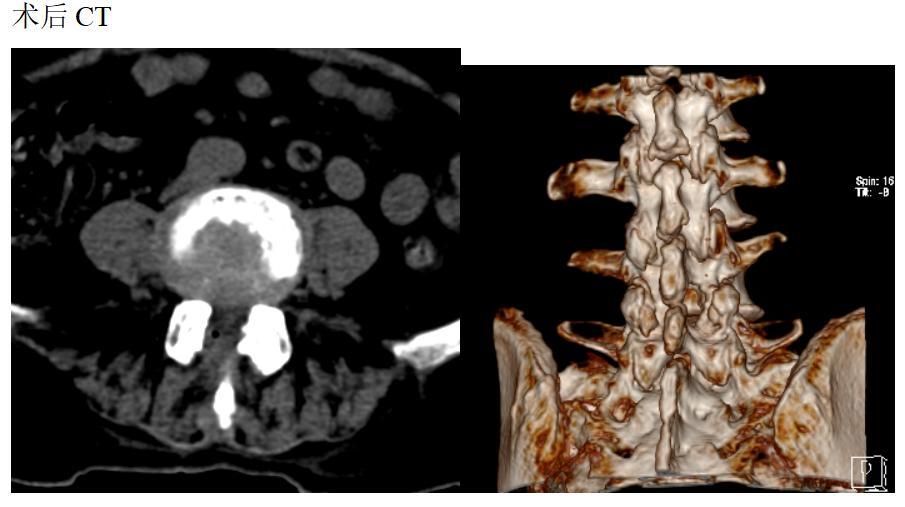

患者女性78岁,主诉:双下肢酸困麻木1年

现病史:1年前出现双下肢酸困麻木,以右侧为主,行走及站立时症状加重,平卧休息稍减轻,未治疗,上述症状持续加重,步行困难,步行能力约100米,为求诊治,现来我院,遂以“腰椎管狭窄症”为诊断收住我科。发病以来,饮食正常,睡眠一般,体力正常,大小便正常。